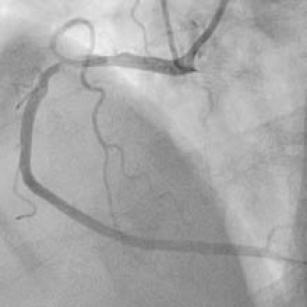

A case of no-reflow—the importance of the coronary microcirculation (Sneak preview #2) 18th Nov 2015 - David G O’Brien, MD, FRCP Today’s video is an impressive case-demonstration of the acute no-reflow phenomenon. After watching this video, ...

Coronary anatomy refresher (Sneak preview #1) 16th Nov 2015 - David G O’Brien, MD, FRCP Very soon, we’ll be launching our brand-new Coronary Angiography Essentials course. This course will teach you many ...